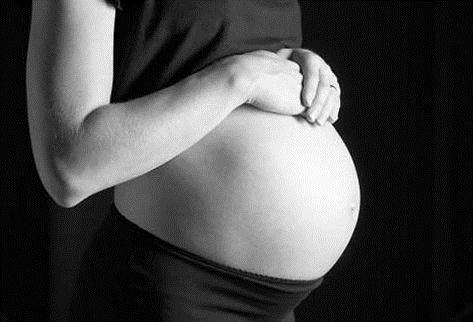

SANTO DOMINGO.- El Observatorio Político Dominicano (OPD), entidad adscrita a la Fundación Global Democracia y Desarrollo (FUNGLODE), pondrá en circulación el cuaderno Mujeres que en proceso de dar vida la pierden. Estudio cualitativo de la mortalidad materna en República Dominicana. La actividad se realizará el miércoles 13 de agosto, a las 6:00 p.m., en el Café Filó de la Biblioteca Juan Bosch de FUNGLODE.

La investigación se planteó ir más allá de los registros oficiales para analizar las situaciones e incidentes relacionados con el fallecimiento de las mujeres por causas relacionadas con el embarazo, parto y puerperio y la forma en que los familiares, allegados y el personal de salud experimentan estos hechos.

El estudio capta las experiencias y vivencias del entorno familiar de las mujeres fallecidas por las causas indicadas, en torno a las situaciones y prácticas desarrolladas en el ámbito hospitalario al momento en que procuraron atención médica.

Asimismo, describe el drama experimentado por los familiares después de la muerte de la mujer durante el proceso de embarazo, parto y puerperio.

El cuaderno Mujeres que en proceso de dar vida la pierden. Estudio cualitativo de la mortalidad materna en República Dominicana es la segunda publicación de la Serie Políticas Públicas del Observatorio Político Dominicano, con el que la entidad desea contribuir al análisis de la realidad social dominicana y al desarrollo de propuestas de políticas públicas que respondan a los problemas nacionales.